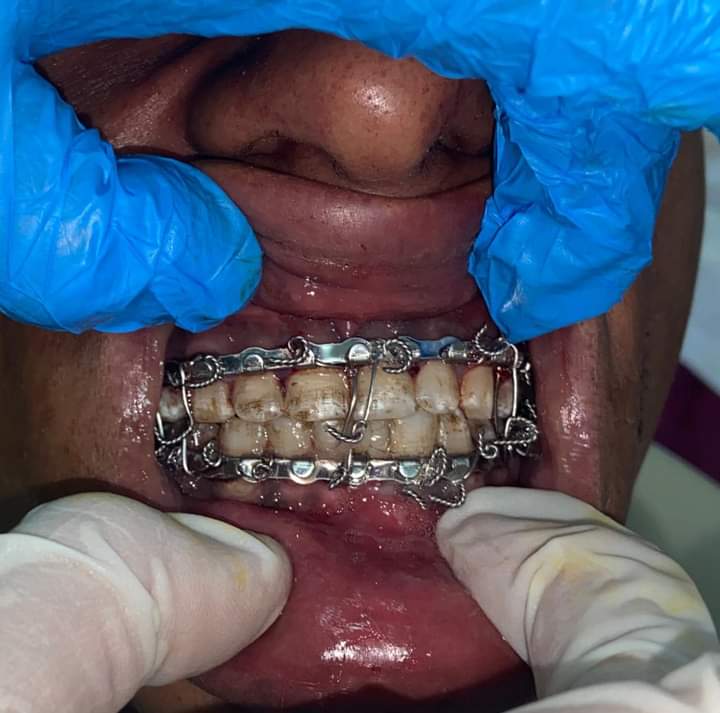

ونجحت مستشفى برج العرب بقيادة دكتور وليد مختار، مدير المستشفي في إجراء التدخل الجراحي لانقاذ حياة شاب يبلغ من العمر 35 سنة، اثر تعرضه لحادث نتج عنه كسر في عظام الجبهة وصل الي المخ وكسر في عظام الوجنه نتج عنه مشكله في فتحه الفم فتحه طبيعه

وأوضح بيان صادر عن مديرية الشؤون الصحية فى الإسكندرية، أن الجراحة تمت بإشراف الدكتورة هبة عارف، مدير عام الطب العلاجي، وأنه تم التنسيق بين قسمي جراحة المخ والأعصاب وجراحه الوجه والفكين لدخول العمليات لرد وإصلاح كسر عظام الجبهة واستئصال كسر منخسف بالجمجمة ورد كسر وخلع بالفك واستعادة فتحة الفم الطبيعية.